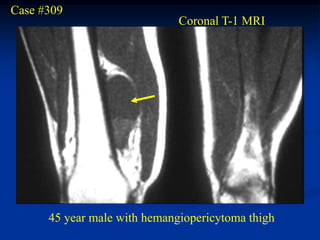

Case #309

Coronal T-1 MRI

45 year male with hemangiopericytoma thigh

Axial T-1 MRI

Axial proton density MRI

tumor

Axial T-2 MRI

Case #309 Coronal T-1 MRI 45 year male with hemangiopericytoma thigh

• 420.

• 421.

• 422.

tumor Axial T-2 MRI